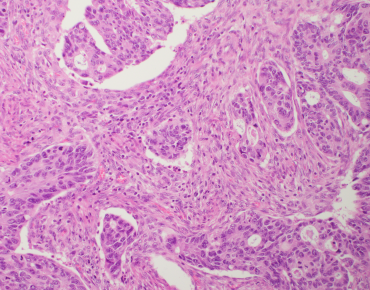

Over the past few years, Roberto Salgado, Sherene Loi and Carsten Denkert have developed the International Immuno-Oncology Biomarker Working Group on Breast Cancer, with members including expert clinical research groups, pathologists, clinicians and statisticians worldwide currently knowledgeable in the field of Immune-oncology Biomarkers. The purpose of this Working Group is to develop, in a timely manner, standards on the assessment of Immuno-Oncology Biomarkers to aid pathologists, clinicians and researchers in their research and daily practice.

All materials on this website, including images, annotations, and similar research and educational data, are anonymized and are therefore freely available to browse, download, and use for scientific and educational purposes.